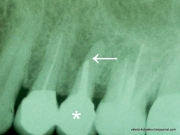

Пришёл пациент с жалобами на боли в зубе и припухлость десны. Пациент недавно вернулся из другой страны, где лечил зубы, ибо в Америке дорого. Болит один из свежевылеченых зубов. Делаем рентгеновский снимок. Видим, что на проблемном зубе (отмечен звездочкой), поставлена вкладка. Также ...